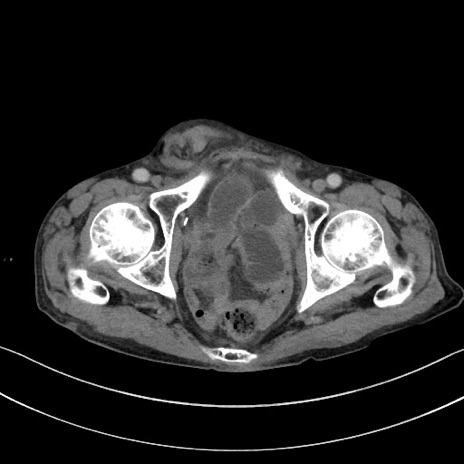

症例3(横断像)

【症例】 70歳代男性

【主訴】右鼠径部腫瘤、疼痛

【現病歴】本日朝より上記主訴あり、受診。

【既往歴】膀胱癌にて膀胱全摘、両側尿管皮膚瘻

【データ】WBC 5600、CRP 0.56